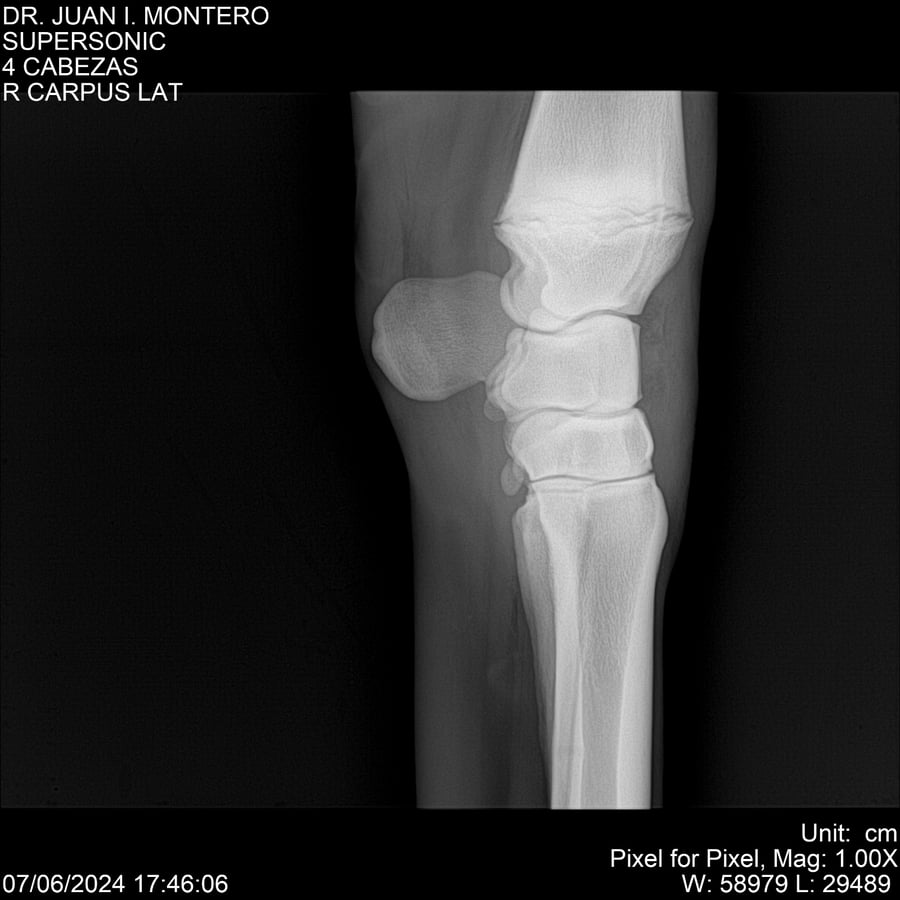

LOTE 5, SUPER SONIC Lote Anterior Volver al remate Lote Siguiente Ficha Contacto Montevideo - Ficha del Lote Identificador: #281089 Categoría: Yeguarizos Montevideo - 69 Visualizaciones ClicData Contacto Empresa: Abelenda N. R., Walter Hugo Nombre*: Teléfono* : E-mail* : Mensaje Enviar Registrese gratis Este contenido Exclusivo está disponible sólo para usuarios registrados Ingresar